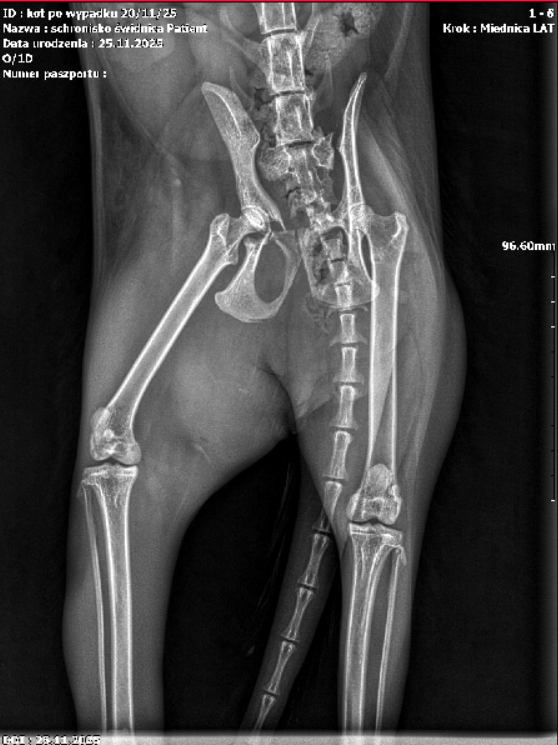

– Coco w stanie silnego bólu trafiła natychmiast do weterynarza. Po wykonaniu badań RTG i pełnej diagnostyki okazało się, że jej obrażenia są poważne i rozległe. Stwierdzono m.in.: obustronne zwichnięcie stawów biodrowo-krzyżowych, złamanie panewki prawego stawu biodrowego, rozejście się nieprawidłowo zrośniętego starego złamania z przemieszczeniem kości kulszowej, zerwanie ogona (uraz kręgosłupa ogonowego) – opisują pracownicy placówki.